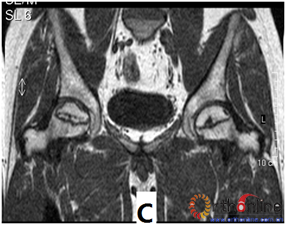

图3 各型坏死打压植骨的结果,(A)Ⅰ型(右侧)和Ⅱ型(左侧)术前MRI显示外侧柱存留;(B)术后7年随访,股骨头维持外形,关节功能好;(C)Ⅲ型(双侧)术前MRI显示外侧柱破坏;(D)术后5年,右侧股骨头维持外形,左侧塌陷

Fig 3 The results of different osteonecrotic type by impacting bone graft,(A)Type Ⅰ(right),type Ⅱ(left) MRI showed the preservation of the lateral pillar preoperatively; (B) Seven years after operation, the femoral head still maintain sphere, hip function is excellent; (C) Type Ⅲ (both side) MRI showed the involved of lateral pillar by necrosis; (D)Five years after operation, the femoral head still maintain sphere in right side, collapse occurred in left side.